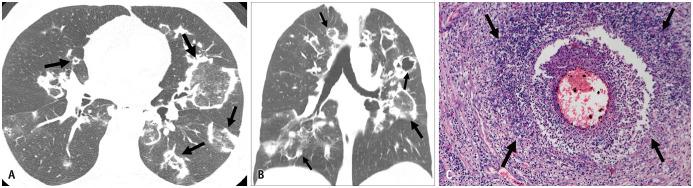

Non-infectious granulomatous lung disease represents a diverse group of disorders characterized by pulmonary opacities associated with granulomatous inflammation, a relatively nonspecific finding commonly encountered by pathologists. Some lesions may present a diagnostic challenge because of nonspecific imaging features; however, recognition of the various imaging manifestations of these disorders in conjunction with patients' clinical history, such as age, symptom onset and duration, immune status, and presence of asthma or cutaneous lesions, is imperative for narrowing the differential diagnosis and determining appropriate management of this rare group of disorders. In this pictorial review, we describe the pathologic findings of various non-infectious granulomatous lung diseases as well as the radiologic features and high-resolution computed tomography imaging features.